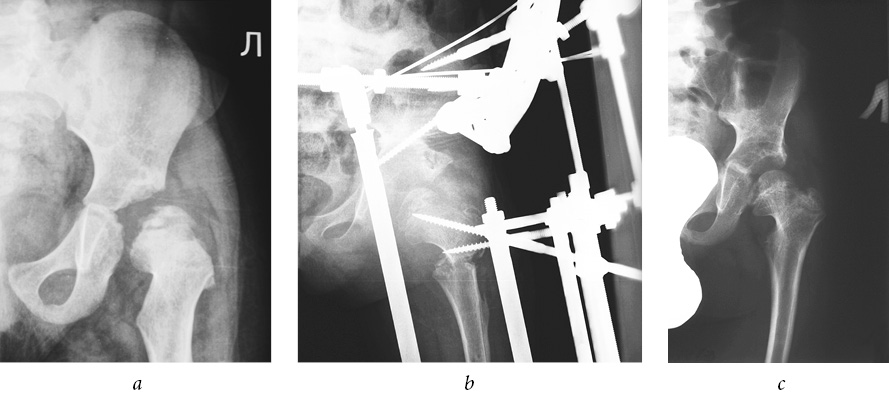

There were no cases among the joints examined that presented with an excellent outcome. Good results were noted only when performing extra-articular interventions (see Table 2). In general, positive outcomes were observed in 94% (Figs. 1–3).

Fig. 3. Patient F., 4 years old, with a diagnosis of congenital dislocation of the right hip, degree III of dislocation, and degree IV Perthes disease: a — frontal radiograph of the hip joint before treatment; b — frontal radiograph of the hip joint during treatment (after performing an open reduction of the dislocation, shortening correcting osteotomy of the hip, osteotomy of the iliac bone, tunneling of the femoral neck and head, hardware decompression of the articulation); c — frontal radiograph of the hip joint 4 years after treatment